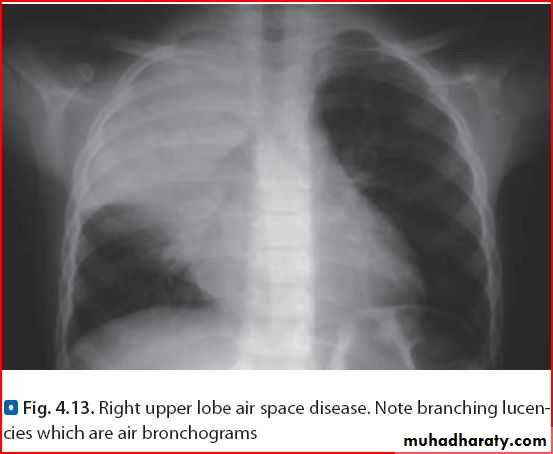

Lobar Pneumonia (rt upper lobe)

Consolidation limited by fissureMost common cause is strept. pneumonae